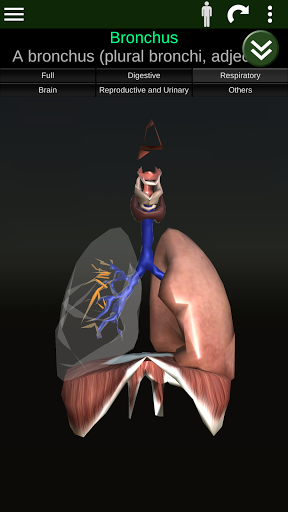

Показує 3D анатомічну модель основні органи людського тіла та опис кожного з них.

* Дихальна система, яка включає трахею, бронхи, легені та анімацію цієї системи.

* Описи кожного органу.